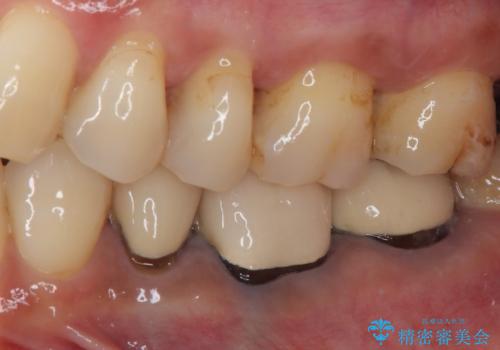

- 奥歯がかけてしまい、しみるようになったとのことで来院された患者様です。

上顎奥の粘膜に近い部分で、つめものの下には大きく虫歯が広がっていました。

虫歯をしっかりと取り除き、ゴールドインレーにて修復することとしました。

ゴールドインレーは銀歯のインレーやセラミックインレーと比べ、「技工操作の精度が高く、適合が著しく良い」というメリットがあります。特に上の奥歯は歯科医師の操作が行いにくいため、「適合の良さ」は再治療のリスクを防ぐ上でとても重要な要素となります。

上の奥歯は金属色が見えることもないため、審美的な問題は全くありません。

咬み心地はとても良好で、全く違和感がなく、患者様には大変満足していただきました。